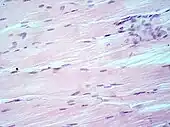

Muscle tissue, cell nuclei (blue-purple), cell body (pink).